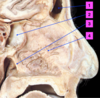

Identify 1

Superior Concha

Identify 2

Medial Concha

Identify 3

Inferior Concha

Identify 1

Frontal Sinus

Identify 2

Sphenoidal Sinus

Identify 3

Choanae

Identify 4

Nasal Septum

Identify1

Pharyngeal Tonsils

Identify2

Auditory Canal

Identify3

Laryngeal Inlet

Identify4

Pharyngo-Oesophageal Junction

Identify 5

Oesophagus

Identify 1

Palatoglossal Folds (Pillars of Fauces)

Identify 2

Palatopharyngeal Folds (Pillars of Fauces)

Identify 3

Palatine Tonsils

Name the Red cavity

- Red = Nasopharynx

Name the Green cavity

- Green = Oropharynx

Name the Yellow cavity

- Yellow = Laryngopharynx